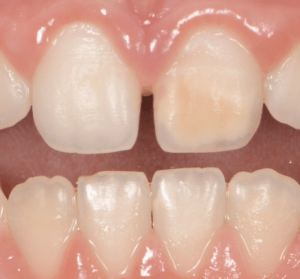

Le congrès de l’EAPD (Académie Européenne d’Odontologie Pédiatrique) a défini des critères de diagnostic en 2003. A savoir des opacités délimités, des fractures post-éruptives, des restaurations atypiques ainsi que que des extractions des molaires. (3) Le diagnostic différentiel doit surtout s’établir entre des amélogénèses imparfaites et des hypominéralisations d’origine traumatique pour les dents antérieures. Cliniquement, les dents vont présenter des colorations blanches ou brunes opaques sur une partie ou sur toute la surface de la dent (Figures 1-2-3-4).

formation dentaire pédodontie Figure 3.

Figure 3-4 : Molaires atteintes de MIH (HSPM + MIH pour la figure 3)